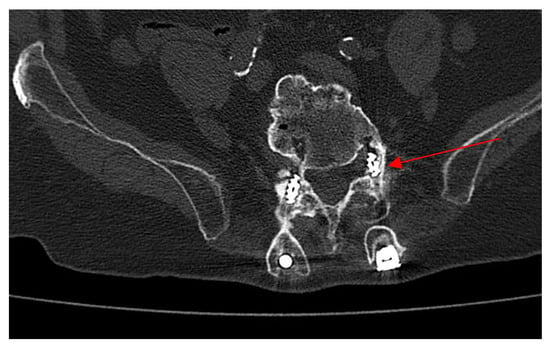

2.4. Neurosurgery Evaluation